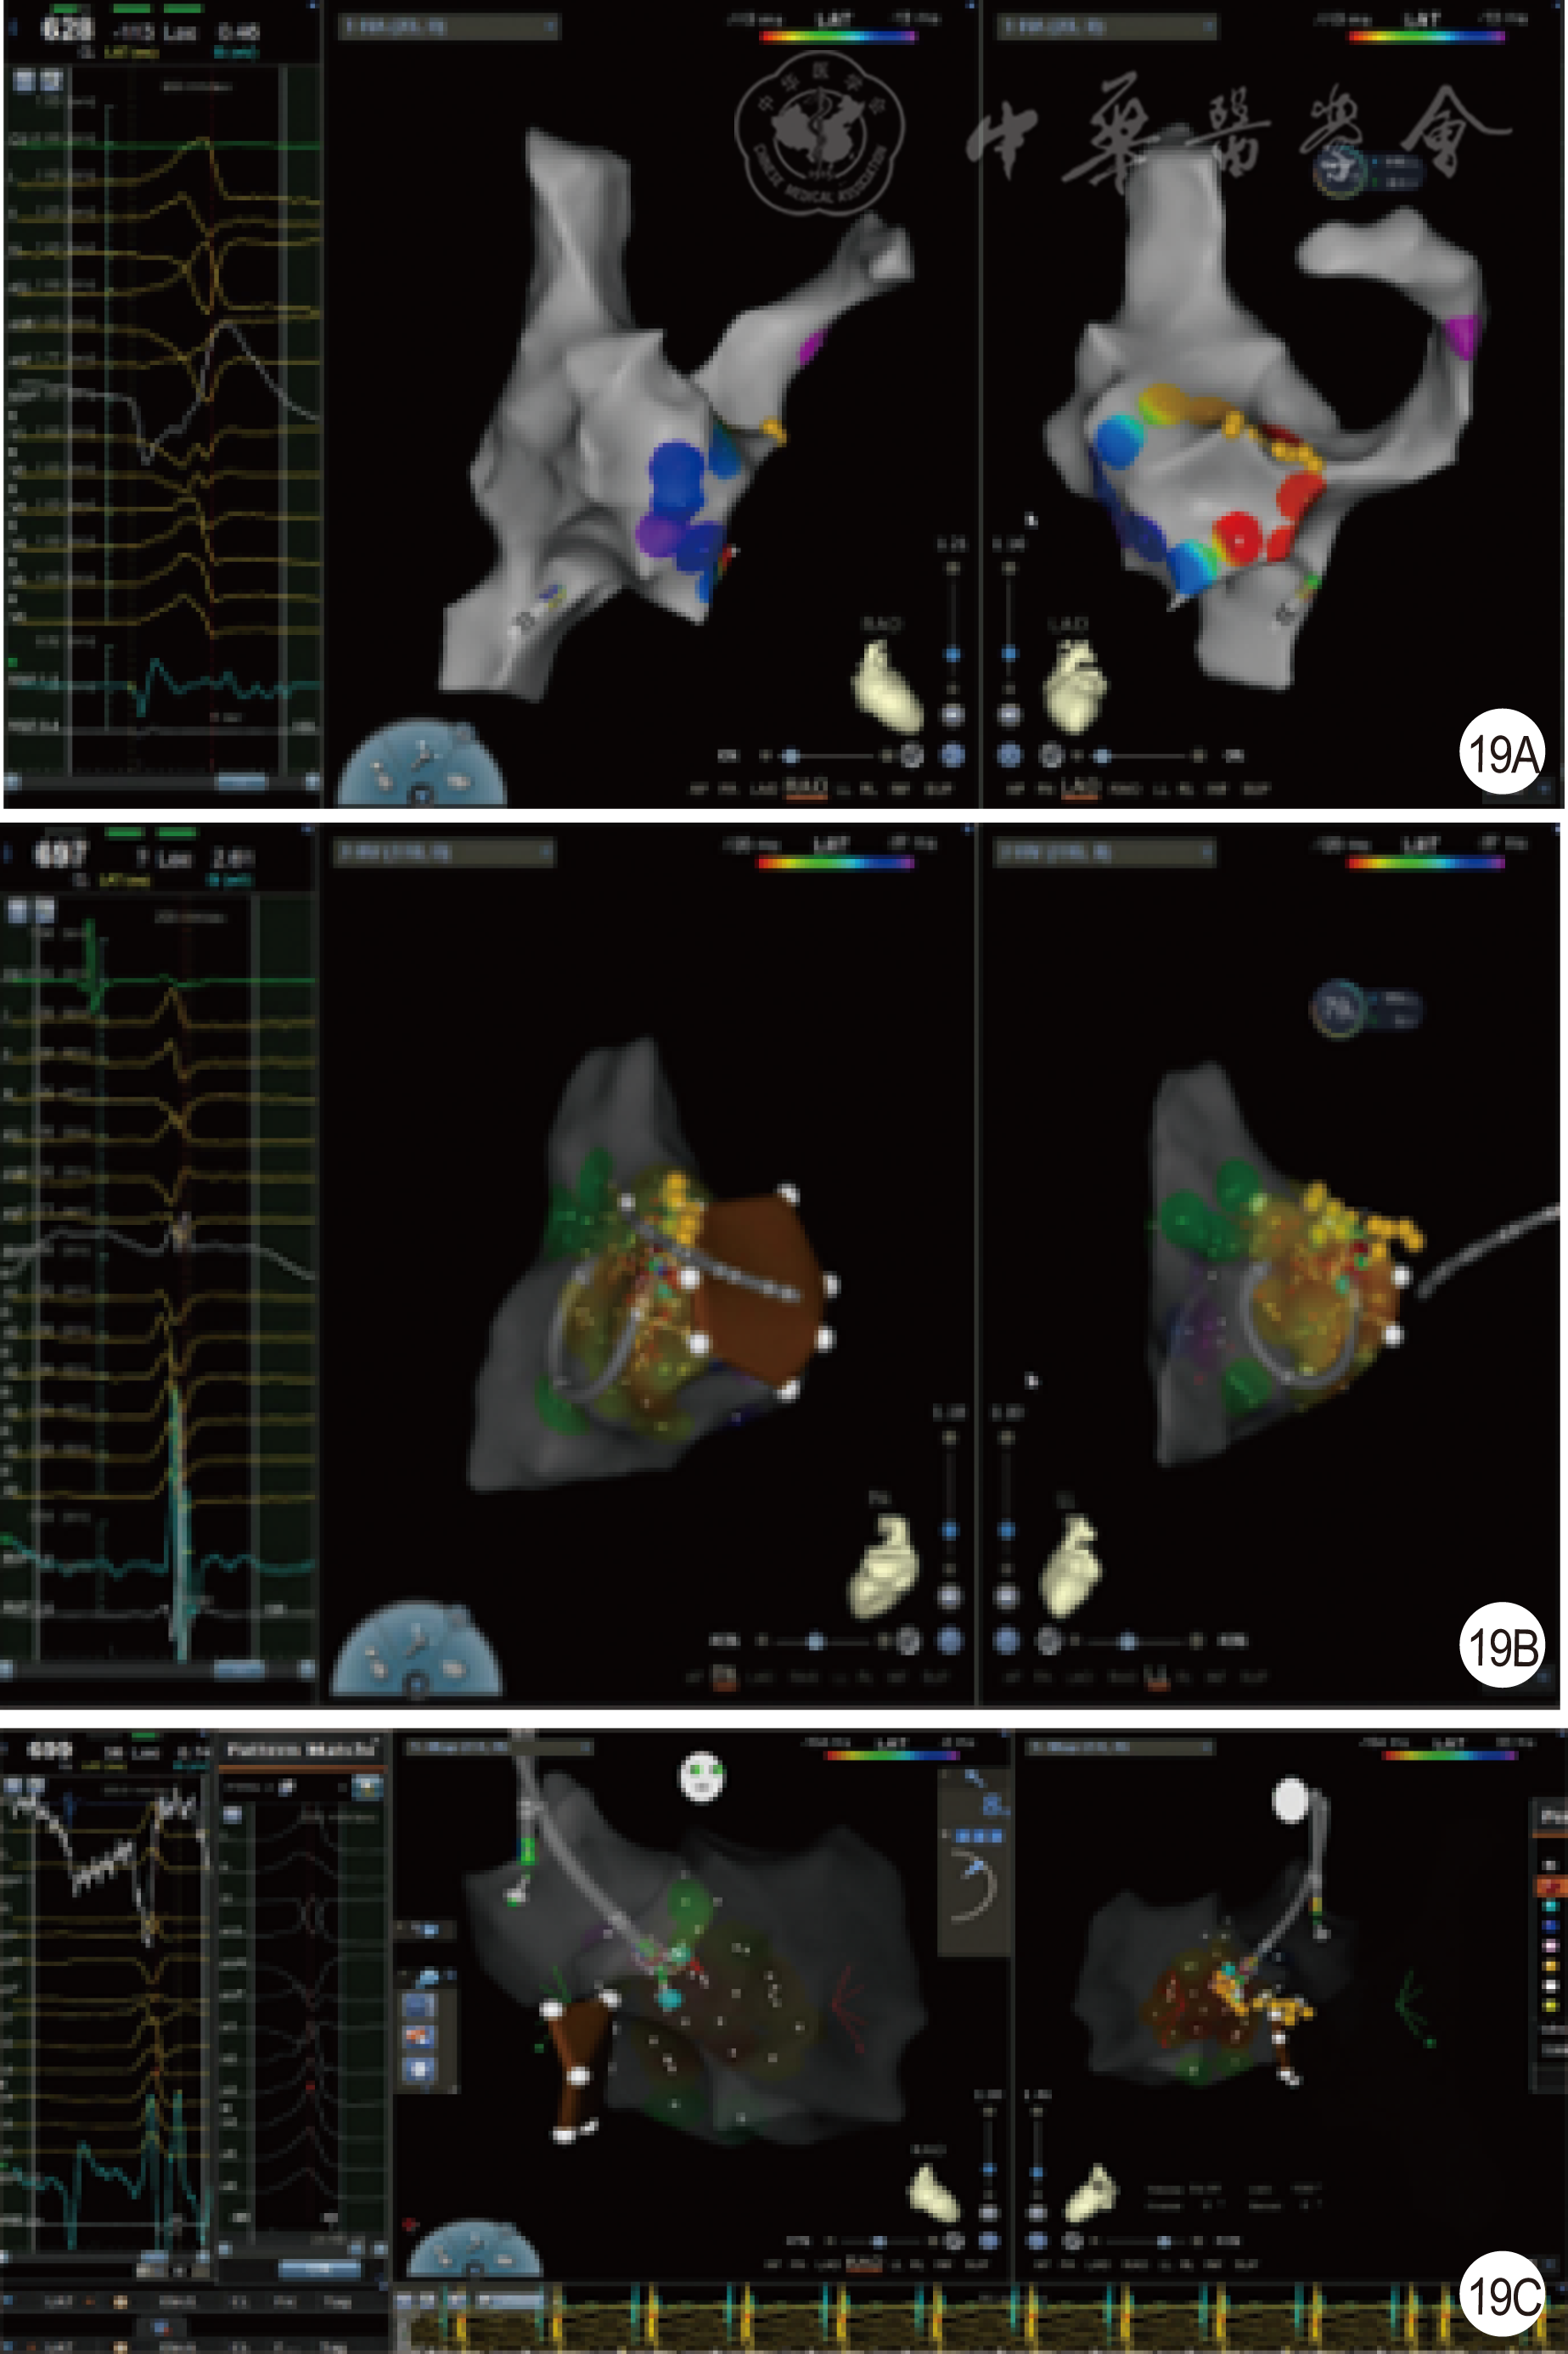

图19 希代束旁室性早搏消融病例二(19A为室性早搏激动标测提示希代束附近最早;19B为消融导管膈瓣下倒U形;19C为消融导管右冠窦消融有效)